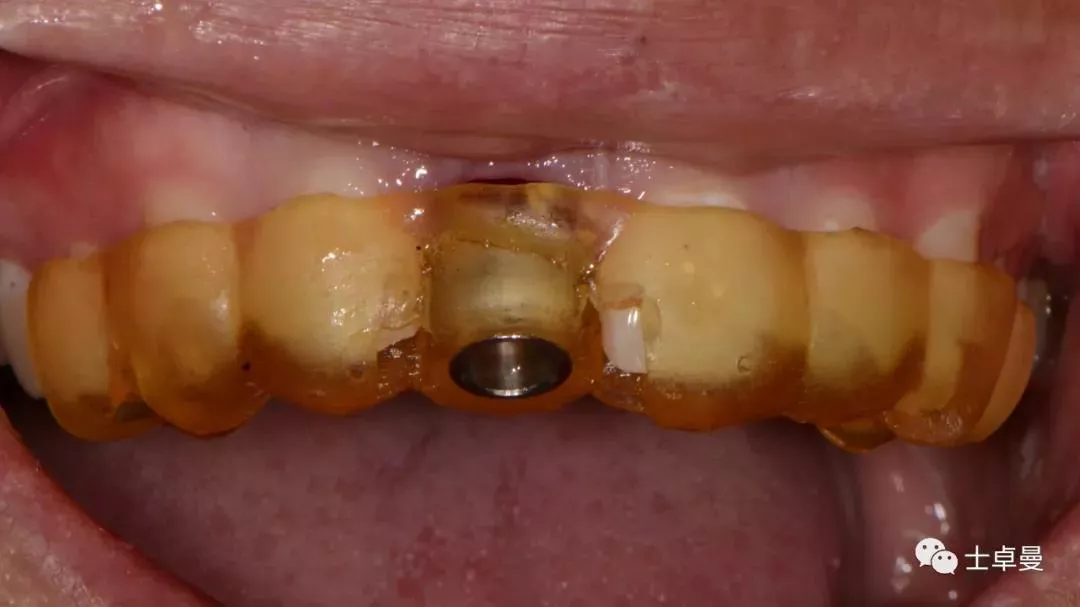

术后即刻制作个性化愈合帽

上部制作马里兰桥临时修复体

术后10天复查,软组织无炎症